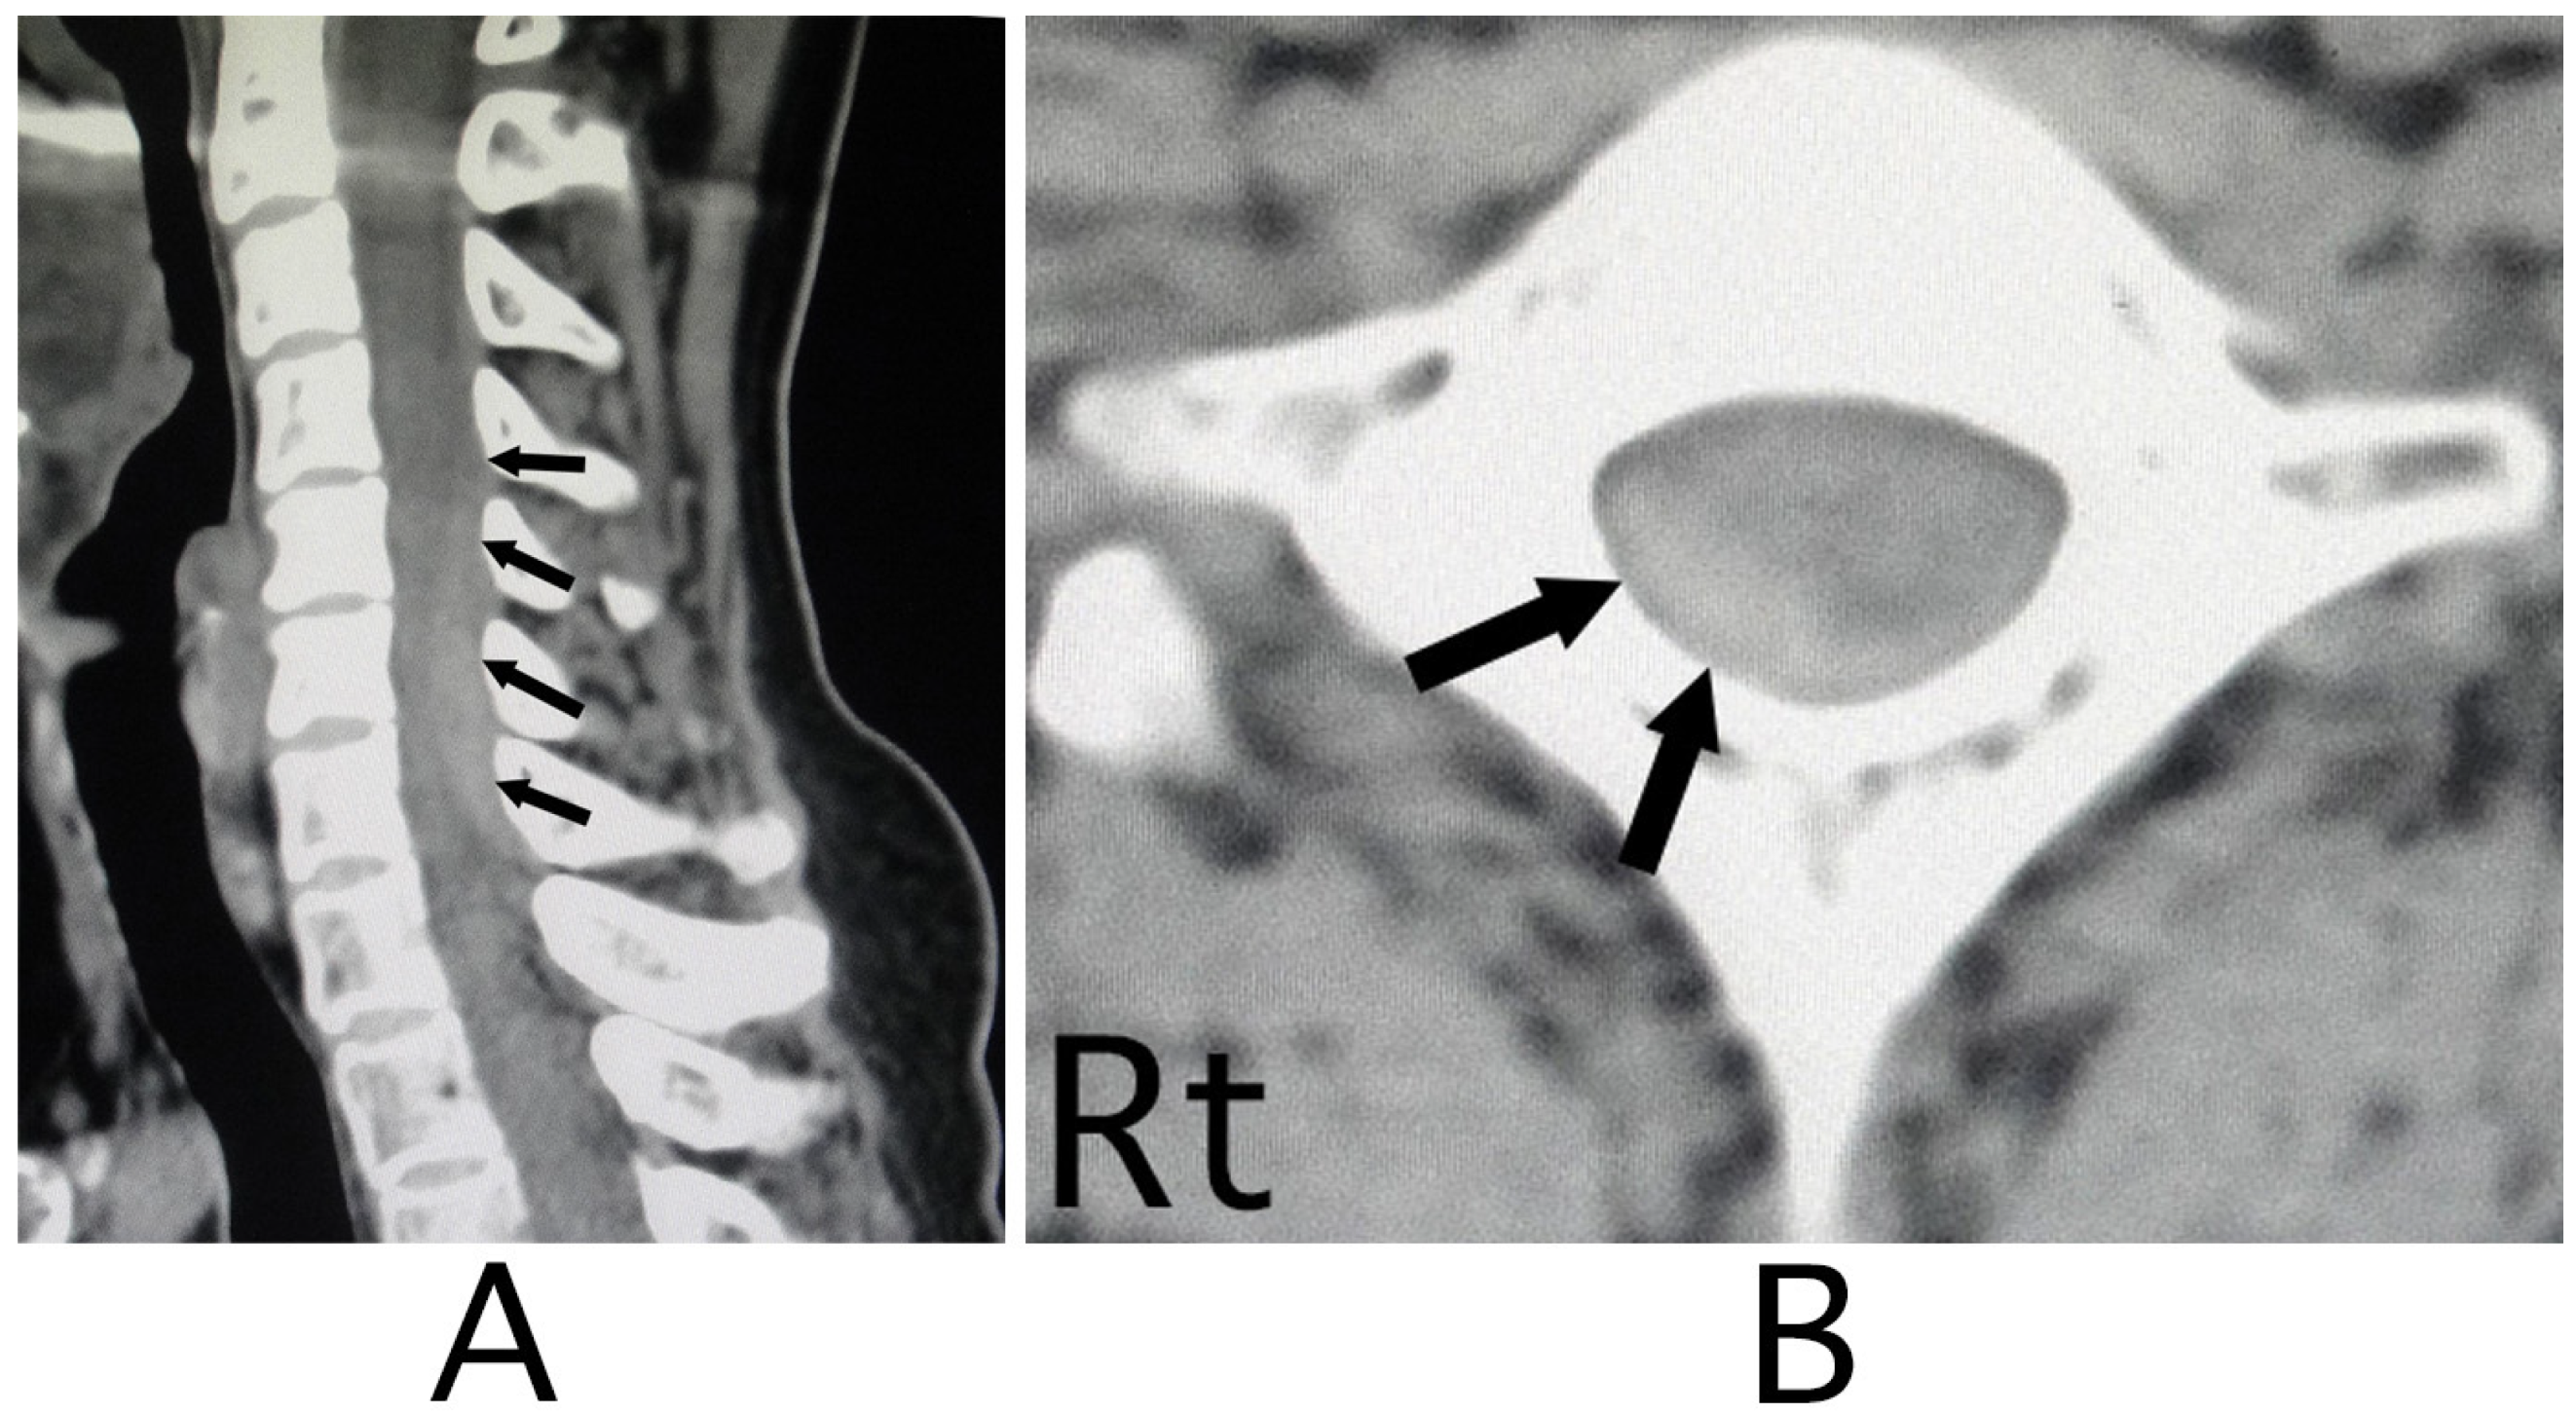

The lesion in the intracranial region or the cervical spinal cord was suspected. Computed tomography (CT) images of the head and X-ray of the cervical bone were normal; however, sagittal CT images of the cervical bone showed a slightly abnormal high-density area (HDA) behind the spinal cord at the level between C4 and C7 (Figure 3A). This abnormal HDA was located in the posterior part on the right side in axial CT images (Figure 3B). MRI analysis was performed because the presence of a hemorrhagic lesion was suspected, based on the CT findings of the cervical bone. Sagittal T1-weighted MRI showed an iso-intensity mass in the epidural space behind the spinal cord at the level from C4 to C7 (Figure 4A). The lesion was noted as a heterogeneous high-intensity mass in sagittal T1-weighted images (Figure 4B). Axial T1-weighted MRI showed an iso-intensity mass in the posterior part on the right side in the epidural space and mild compression of the spinal cord (Figure 5A). The lesion was noted as a heterogeneous high-intensity mass in axial T2-weighted images (Figure 5B).

Figure 5. Axial MRI. An iso-intensity mass was identified in the diagonally posterior part on the right side (white arrows) (T1-weighted image; (A)). The lesion was visualized as a heterogeneous high- intensity mass (black arrows) (T2-weighted image; (B)). Mild compression of the spinal cord by the lesion was shown (A,B). (Rt = right).